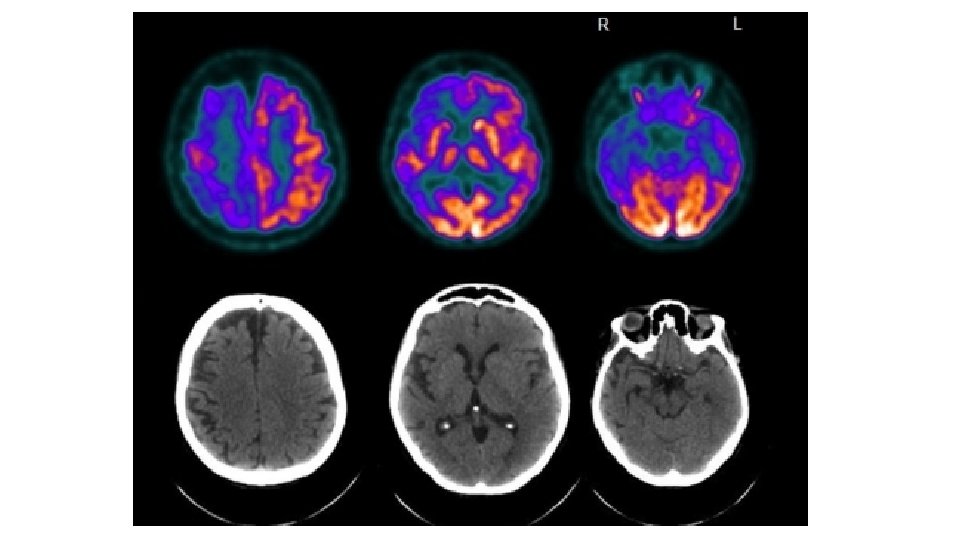

EOFAD show CMRglc reductions before symptoms - Presymptomatic PS-1 FAD (n=7) vs matched controls (n=7) - Age 35 -49 yrs, education>10 yrs, MMSE 29 -30, CDR=0 - MRI and FDG-PET scans Studiare chi si ammalerà F, 42 yrs, MMSE 30, CDR 0 PS-1: F, 35 yrs, MMSE 30, CDR 0 13 yrs before expected onset age Mosconi et al, J Nucl Med 2006

Studiare chi si ammalerà PS 1 - F, 35 yrs, MMSE 30, CDR 0 F, 42 yrs, MMSE 30, CDR 0 PS 1 M 40 yrs, MMSE 30, CDR 0 B e C. = RMN e PET di due soggetti di di 35 e 40 anni portatori di una mutazione per la demenza ereditaria senza sintomi clinici. Mosconi et al, J Nucl Med 2006